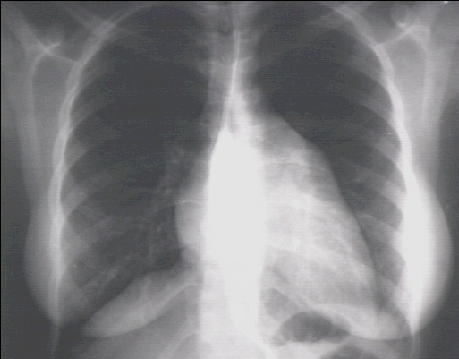

You are incorrect - the best interpretation of the chest X rays in our patient is that they are normal.

Your choice: Left ventricular enlargement + left atrial enlargement

These chest X rays show left ventricular enlargement and left atrial enlargement. This PA view demonstrates the enlarged left ventricle as an increase in the inferolateral cardiac border associated with an increased cardiothoracic ratio.

The markedly enlarged left atrium is manifested by the double contour within the heart border, an elevated left left mainstem bronchus, and an enlarged left atrial appendage.